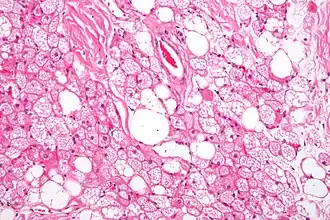

Клетки жировой ткани, накапливающие жир, называют адипоцитами. Одиночные адипоциты имеют шарообразную форму. Жировую ткань принято подразделять на белую и бурую согласно её цвету. Адипоцит белой жировой ткани содержит одну большую каплю нейтрального жира (такие адипоциты также называют унилокулярными), которая занимает центральную часть клетки и окружена тонким слоем цитоплазмы, в утолщённой части которого залегает уплощённое ядро. В цитоплазме адипоцитов содержатся в небольших количествах и другие липиды: холестерин, фосфолипиды, а также свободные жирные кислоты. Эти мелкие жировые включения особенно выражены у незрелых адипоцитов. Зрелый адипоцит имеет крупные размеры, от 50 до 150 мкм. Так как липиды вымываются ксилолом и другими растворителями, использующимися при приготовлении гистологических препаратов, унилокулярные адипоциты при рассмотрении с помощью светового микроскопа выглядят пустыми[3].

Рыхлая волокнистая соединительная ткань образует прослойки, которые делят жировую ткань на дольки разного размера и формы. В дольках адипоциты близко прилегают друг к другу, однако в жировой ткани также присутствуют клетки так называемой стромальной васкулярной фракции: преадипоциты, фибробласты, клетки эндотелия сосудов и ряд иммунных клеток, такие как макрофаги жировой ткани[1]. На клетки стромальной васкулярной фракции приходится около половины всех клеток жировой ткани[4]. Жировые клетки разделяются тонкими коллагеновыми волокнами, ориентированными во всех направлениях, а также оплетены ретикулярными волокнами[4]. Группы адипоцитов или отдельные дольки тесно охватываются кровеносными и лимфатическими капиллярами[5].